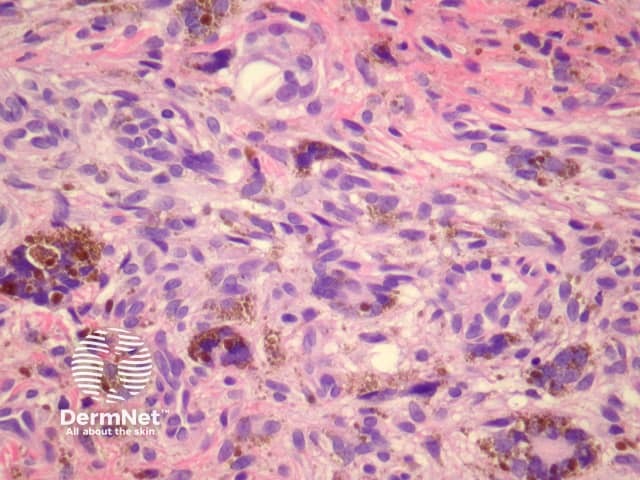

Atypical dermatofibroma is also known as dermatofibroma with monster cells or pseudosarcomatous dermatofibroma. There are focal areas within a common dermatofibroma consisting of large polymorphous cells with large nucleoli (‘monster cells’) (figures 9, 10).

Atypical dermatofibroma can be aggressive with rare reports of metastasis and death. However, many of these cases were described before modern immunohistochemical studies were available and may now be reclassified as sarcomas.

Figure 9

Figure 10